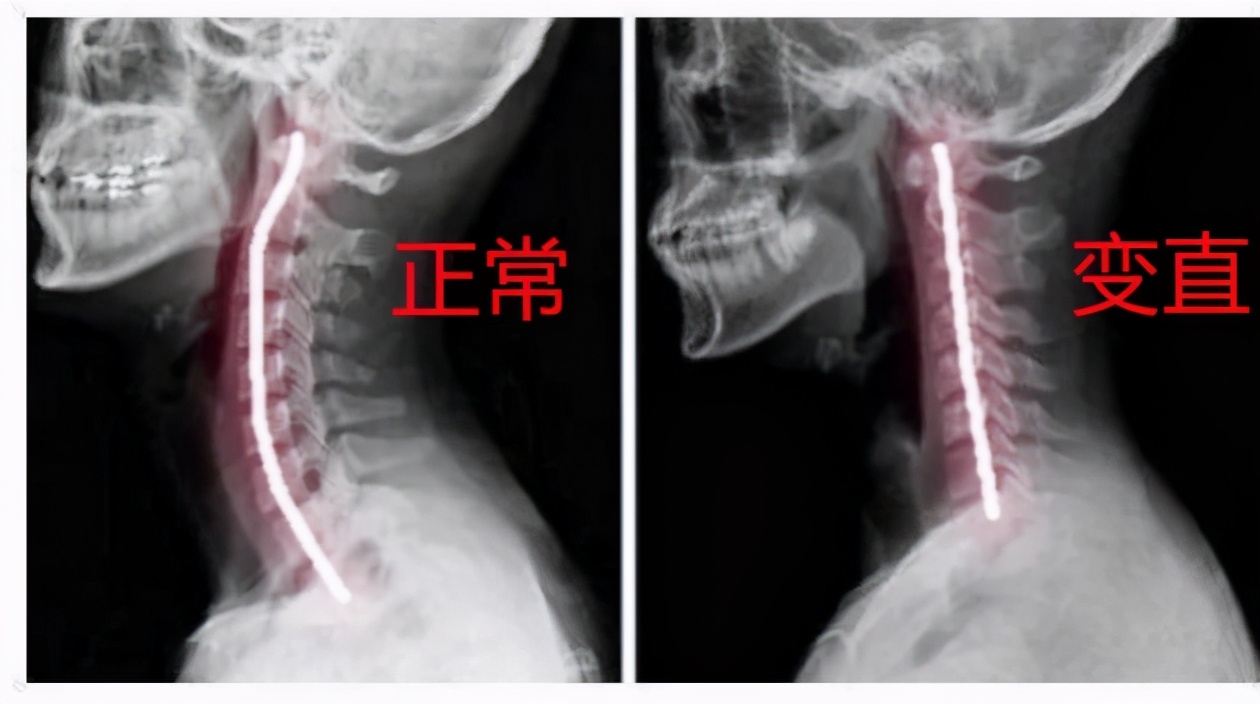

如图,正常颈椎有生理性的前曲,前曲消失就是变直,如果再加重甚至可能出现反弓。